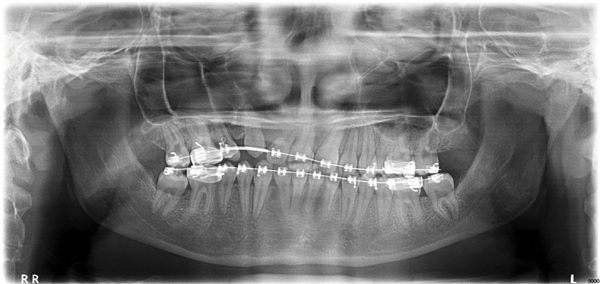

A 15-year-old female presented as a transfer patient after four years of active treatment elsewhere. Pre-treatment records taken when she was nearly 12 showed a case that appeared manageable—near-Class I occlusion, adequate maxillary arch space, and an ectopically positioned upper right canine that did not seem unusually difficult to address (Figs. 1–3). What arrived at the new practice was something considerably more complex.

Fig. 1